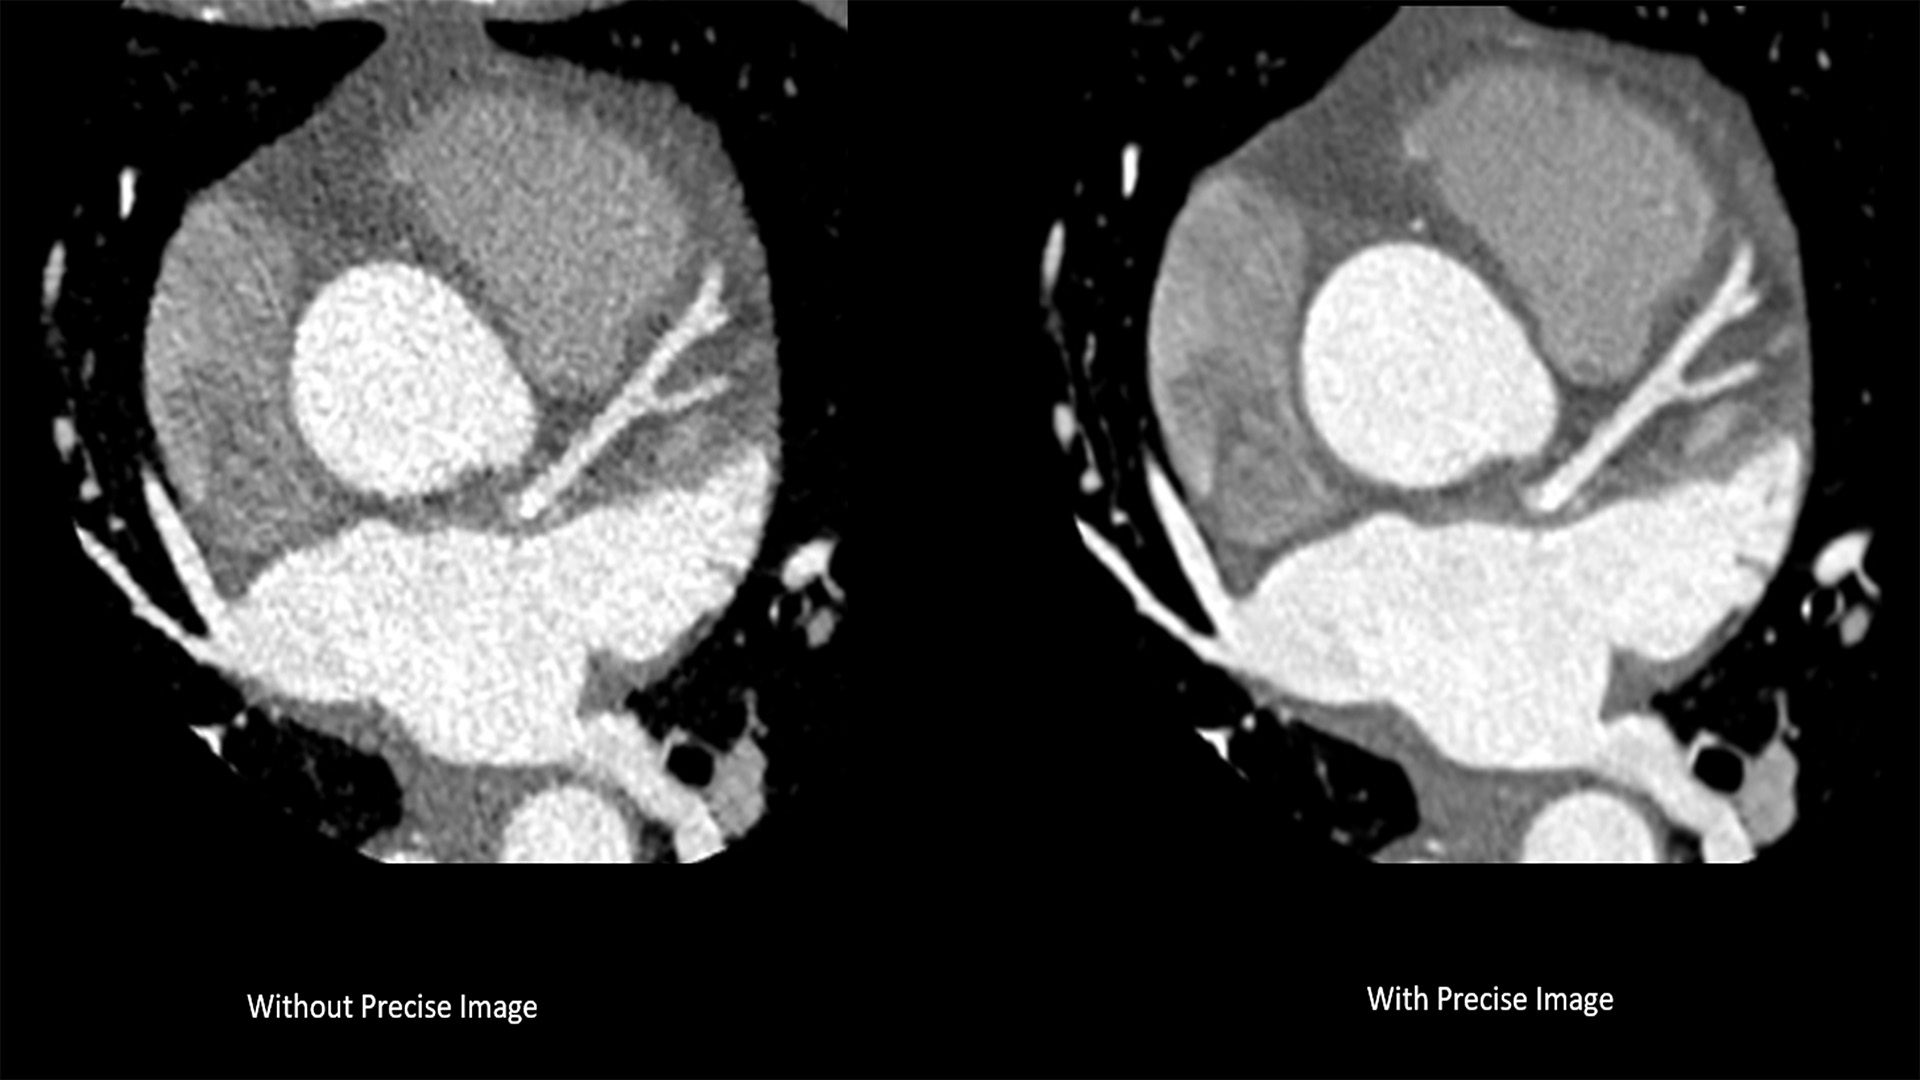

The new CT 5300 system is already installed at several European hospitals and has been well-received. “CT 5300 offers CT imaging from head to toe, combined with high-end functionality such as coronary angiography, delivering an extremely broad spectrum of applications, helping us to better manage increased volumes of patients,” said Dr. Hilmar Kühl, Head of Radiology at St. Bernhard-Hospital Kamp-Lintfort, Germany. “With this latest system from Philips, we see an improvement in image quality with Precise Imaging, and for the first time, we can now visualize cardiac anatomy by using Precise Cardiac nearly artifact-free, which is very valuable to help improve cardiac care for our patients.”

The new system introduces Nanopanel Precise, the industry’s first detector built from the ground up specifically for AI-based reconstruction. This brand-new detector leverages the full capabilities of Philips Precise Image reconstruction software to deliver high-quality images at much lower radiation dose. At 80% lower dose, Precise Image achieves up to 85% lower noise and 60% better low-contrast detectability than conventional image reconstruction [2]. Combined with Precise Cardiac motion compensation, Precise Image makes the CT 5300 particularly suitable for high-quality, motion-free, cardiac imaging [3] in patients with high heart rates or heart-rate variability.